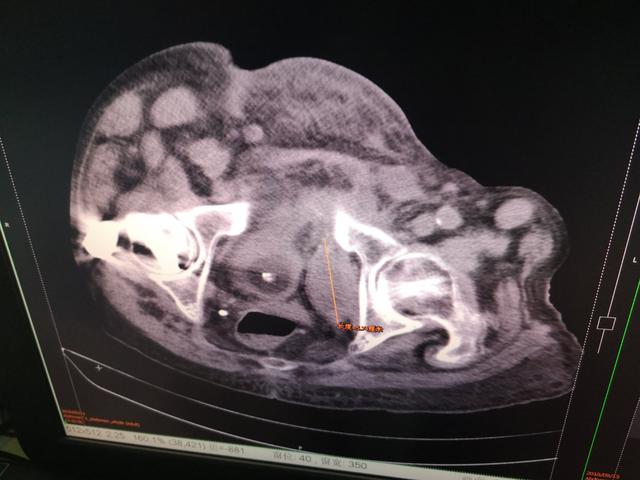

患者再次住院是2018年11月22日,以“嗜睡2天”急诊入院。急诊头部CT、心电图、心肌酶谱检查,除外了心脑血管意外相关疾病后,以“嗜睡待查 肝性脑病?”再次收入消化内科,急查血氨:88umol/L。入院后行全腹CT检查,发现:腹水明显减少,而且腹腔占位明显缩小。该患经两天对症治疗,很快清醒,1周后出院。